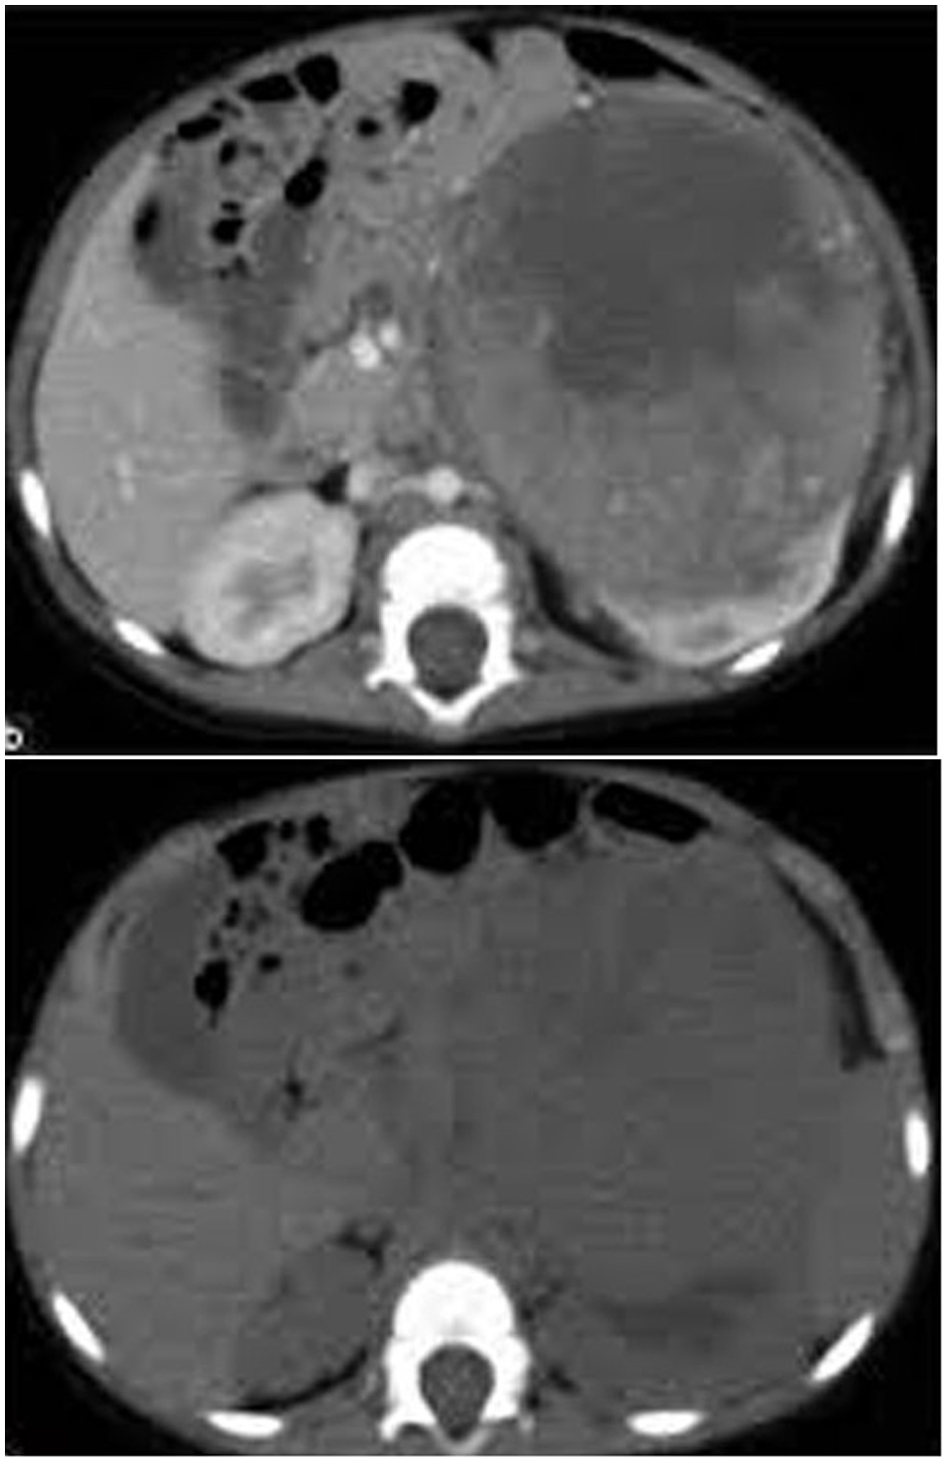

In group I, five patients (33.3%) were found to be understaged at histopathological examination with CT accuracy of 66.7% (P < 0.03) compared to surgical exploration and biopsy. This was due to unresectable tumor margins in spite of being stage II on CT (Fig. 1). On the other hand, histopathological examination confirmed free margins in all patients with stage II in group II (P < 0.01).

![]() Click for large image | Figure 1. CT image showing a left renal mass with enhancing renal parenchyma posteriorly. Lobulated tumor thrombus is present in the left renal vein and IVC. |